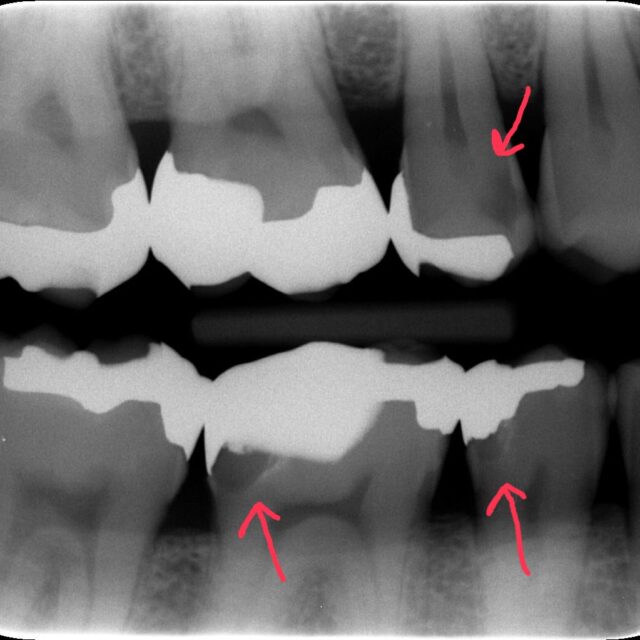

歯ぐきからの出血を放置していませんか?“痛くない歯周病”の落とし穴

目次 歯ぐきからの出血を「様子見」していませんか? たった1か所の出血でも歯周病…